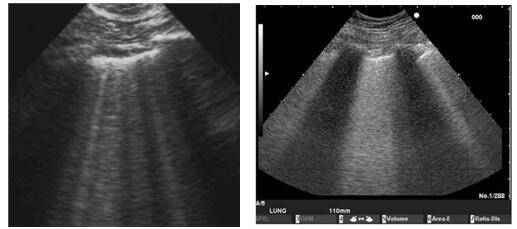

超声B线

肺部超声可见大量b线,提示患者肺水肿.